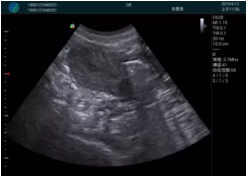

M20查看:囊內(nèi)回聲均勻,邊界清晰,囊壁光滑

M20引導(dǎo)抽吸術(shù)后囊腫消失,原區(qū)域空腔形成,脂肪層與腺體層架構(gòu)發(fā)生改變